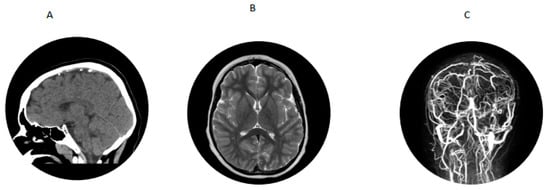

2. Patient 1

Figure 1. (A) CT scan showing venous hyperdense cortical vein over right parietal convexity. (B) MRI showing extensive white matter changes. (C) MRV showing thrombosis of right parietal cortical vein extending into the superior sagittal sinus.